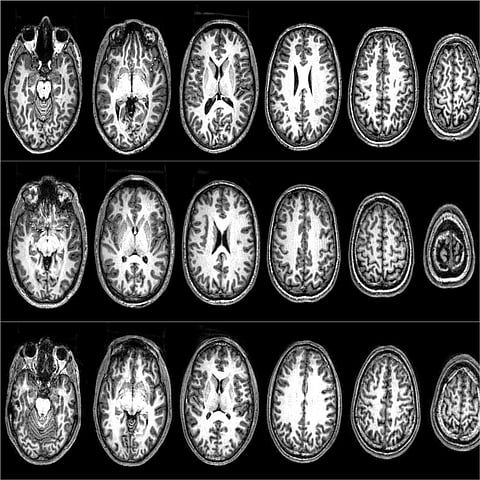

For our brain scans we used a tool called functional magnetic resonance imaging (fMRI) which records and identifies which areas of the brain are active during specific tasks. Our first fMRI study explored what could make non-sacred values become more like sacred values.

Unsurprisingly, participants rated higher willingness to fight and die for sacred rather than non-sacred values. Neurally, sacred values activated the left inferior frontal gyrus (IFG) – an area associated with rule processing and previously correlated with sacred values in American university students. But those who were excluded increased their willingness to fight and die for their non-sacred values, and the left IFG became activated even during non-sacred value processing.

In the first part of the study, they were scanned while rating their willingness to fight and die for their sacred and non-sacred values. These participants showed a different pattern of neural activity from the Moroccans in our first study, who exhibited the same patterns as US university students.

As the highly radicalised Pakistani men rated their sacred values, there was deactivation in a network that includes the dorsolateral prefrontal cortex (DLPFC), a part of the brain which is associated with deliberative reasoning and integrating cost-benefit calculations. When they rated a high willingness to fight and die for their values, we found increased activation in the ventromedial prefrontal cortex (vmPFC), a part of the brain that is associated with subjective valuation (how much value does this have for me?). In daily life, the DLPFC and vmPFC work in tandem when making decisions.

A follow-up analysis found that these two regions of the brain were highly connected when participants rated low willingness to fight and die – that is, subjective value was regulated by decision control mechanisms. But when they rated high willingness to fight and die, we found that these two regions were more disconnected. This suggests that, when someone is ready to kill and be killed in defence of an idea, they are no longer using decision control mechanisms typically involved in deliberative reasoning.

They essentially disengage this part of their brain. But, their willingness to fight and die lowers as their deliberative and subjective valuation regions reconnect. So what mechanisms bring people to lower their willingness to fight and die for a cause?

Despite this, we found that people lowered their willingness to fight and die for both sacred and non-sacred values to conform to the responses of their peers. This change was correlated with increased DLPFC activation in the brain. Their deliberative pathways were reopening.